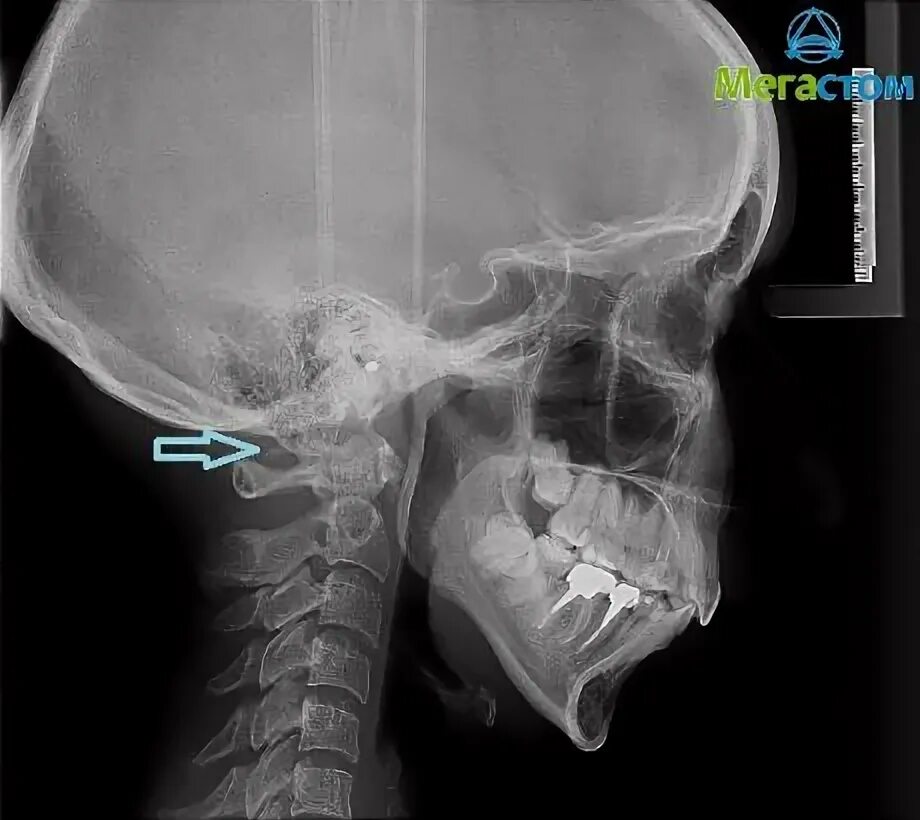

Киммерли что это такое у взрослых